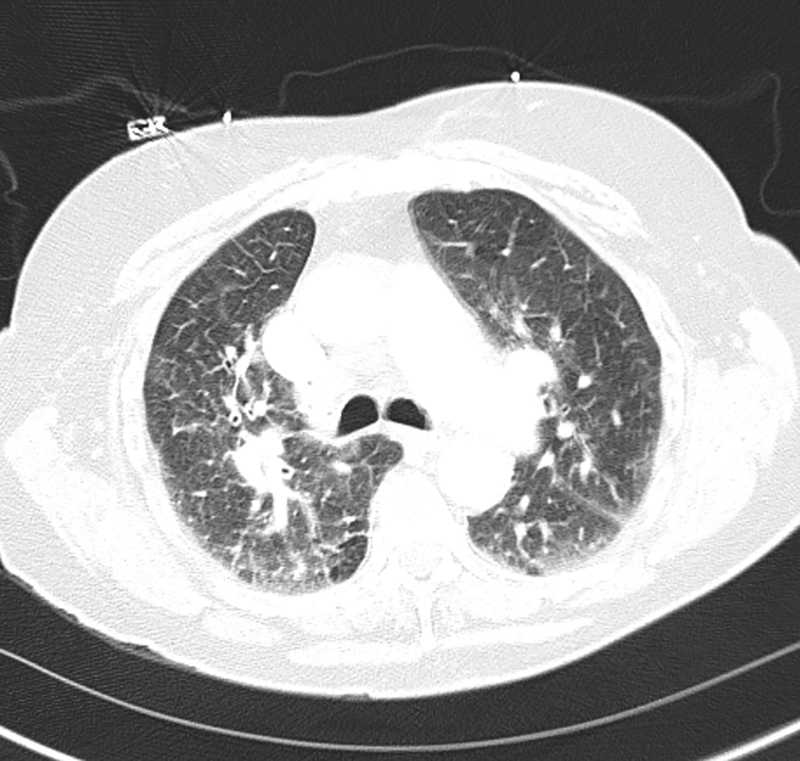

An 83-year-old woman living in rural New Mexico with past medical history significant for Alzheimer’s dementia and Type II diabetes mellitus was hospitalized for four-day history of malaise, anorexia, fever and dyspnea. On initial presentation, the patient was hypoxic on room air with a heart rate of 101 bpm, respirations of 33 bpm, blood pressure of 117/74 mmHg and temperature of 99°F. CXR on admission showed bilateral infiltrates (Figure 1). Computed tomography with angiography was performed and was negative for pulmonary embolism but showed diffuse bilateral ground glass opacities (Figure 2). Diagnostic workup revealed leukocytosis (12.1 K/mcL), platelet count of 115 (K/mcL), hemoglobin of 16.6 (g/dL), and hematocrit of 47.4%. The patient had normal renal function on admission. A transthoracic echocardiogram showed preserved ejection fracture and no acute valvular pathology. Testing was negative for influenza A/B PCR, COVID-19 PCR, viral PCR panel, ANA, Mycoplasma IgM and Streptococcus pneumoniae and Legionella urinary antigens. Due to the location of the patient’s home residence, as well as reports of exposure to mice, serology testing for Hantavirus was sent. The patient was placed on empiric antibiotics for presumed community-acquired pneumonia but deteriorated during her third hospital day, with worsening hypoxia ultimately requiring endotracheal intubation with mechanical ventilation. Initial PaO2/FiO2 ratio was 133 and later deteriorated to 87. A repeat chest X-ray showed worsening diffuse bilateral patchy opacities (Figure 3). Blood, urine and sputum cultures returned negative. The patient developed refractory hypotension despite fluid resuscitation and required increasing amounts of vasopressor support. Lab work reflected worsening hemoconcentration despite intravenous fluid administration. The family ultimately elected for conversion to palliative measures, and the patient passed away with comfort care. Serology testing for Hantavirus later returned positive for IgM and IgG.

Figure 2

Figure 2. Computed tomography of the chest reveals patchy bilateral ground lass opacities.